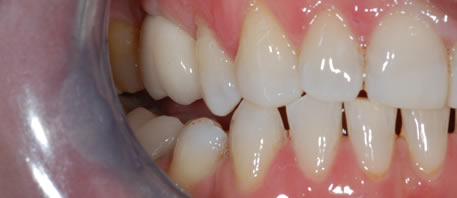

Before Dental Implant

dental implants northern ireland

After Dental Implant